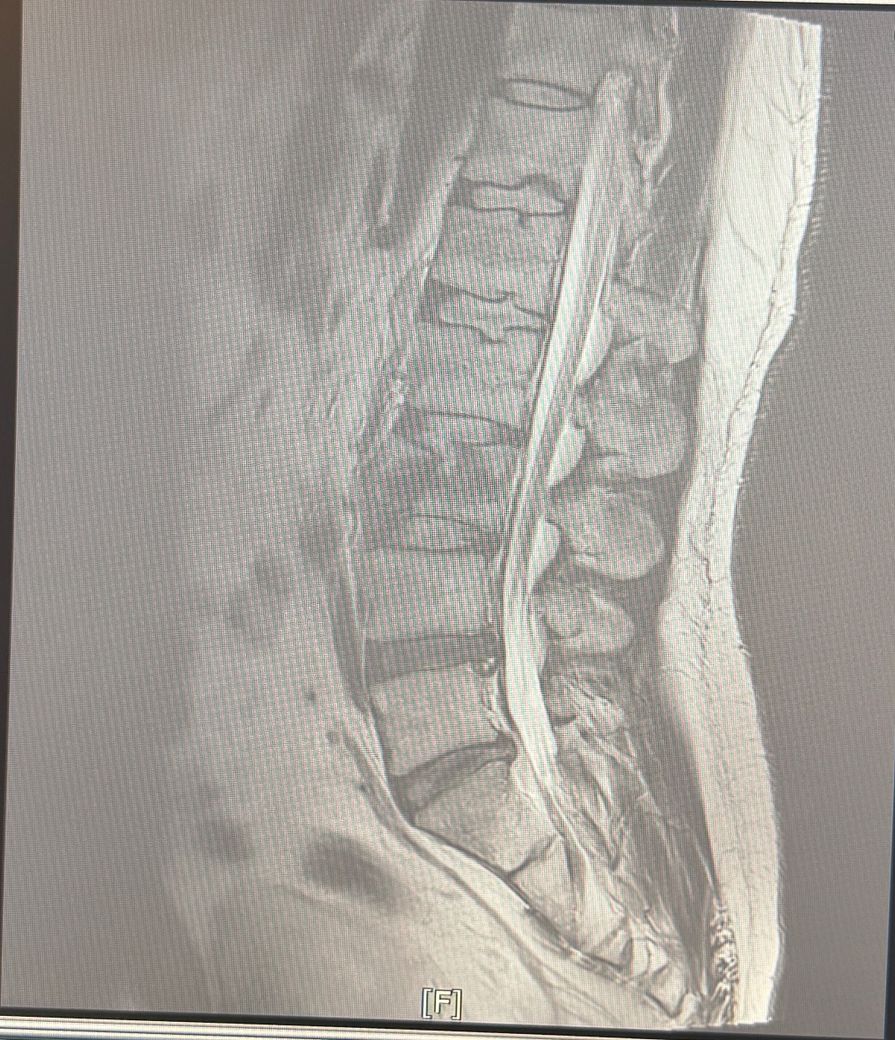

혹시 이건 무슨골절이라고하나요 ??

낙상으로인해 척추가 골절됐는데 세조각으로 조각났어요

제가 아직 누워있어서 면담은 못했지만 이런 골절도 아빡골절이라고하나요? 아님 다른 명칭이 있나요?

낙상으로 척추가 세 조각으로 부러졌다면 척추뼈의 골절은 압박골절이라고 하며 단순한 압박골절을 넘는 더 심한 형태일 가능성도 존재합니다.

압박 골절은 척추체 몸통이 위에서 눌리면서 찌그러지면서 발생하는 골절로 대개 한 조각처럼 부서지는게 특징이고 파열 골절은 척추가 여러조각으로 터지듯 골절되는 상태를 의미합니다.

낙상으로 뼈가 3조각으로 골절되었다면 분쇄골절로 분류할수있는데요 이럴때에는 즉각적인 치료가필요하니 병원에서 전문의와 상담을받아보시고 적절한 치료를처방받으시길 바랍니다 감사합니다~

분쇄골절은 2개 이상의 골전선에 의해 3개 이상의 골절편이 발생하는 것을 말하며

낙상으로 인하여 세조각으로 골절이 발생하였다면 분쇄골절이라고 합니다.

척추가 세 조각으로 부러졌다면 일반적으로 폭팔골절일 가능성이 높아요 압박골절보다 더 심한 형태로 뼛조각이 주변 신경을 압박할 수 있어 신경학적 증상 유무가 중요합니다.

압박골절 말하시는거 같습니다. 척추가 세 조각으로 골절된 경우, 압박골절(compression fracture) 또는 분쇄골절(comminuted fracture)로 분류될 수 있습니다. 압박골절은 척추뼈가 압력에 의해 납작해지거나 쪼개지는 경우를 말하며, 분쇄골절은 뼈가 여러 조각으로 부서지는 경우에 해당되죠. 특히, 낙상으로 인해 골절이 일어난 경우, 충격의 강도에 따라 이런 형태의 골절이 발생할 수 있어요

만약 척추의 골절 부위가 세 조각 이상으로 분리되었다면 분쇄골절이 더 적합한 명칭일 수 있습니다. 이런 골절은 치료 과정에서 신경 손상이나 다른 합병증이 발생할 수 있기 때문에 정확한 진단과 적절한 치료가 중요합니다.